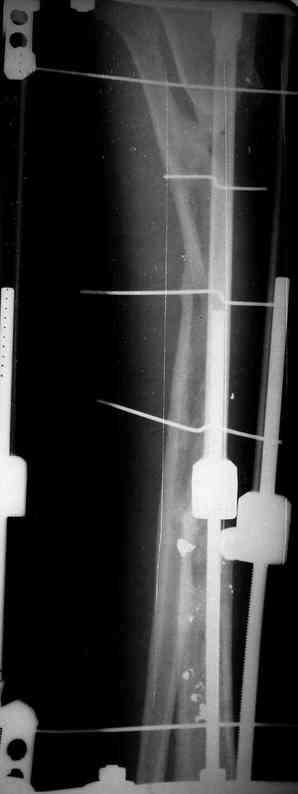

Реализовал описанную выше методику, и в итоге вот что получилось. Высылаю лишь прямые проекции,

в боковых тоже всё в тему.

Очень пригодились карбоновые кольца (Джолдас -огромное спасибо, я твой должник!!!), поскольку остеопороз дистального отломка был просто невероятный. На цифровом рентгене с трудом угадывались контуры.

Рентген в процессе перемещения - внизу карбоновые кольца, тракция фрагмента спицами с упором.